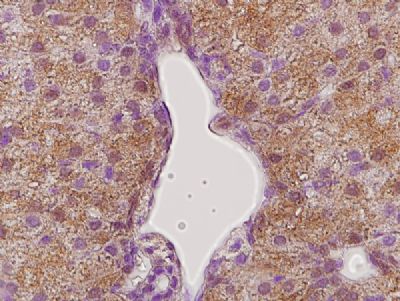

This image was generously provided by Brandon Menzies, PhD, from The University of Melbourne. Paraffin embedded tammar wallaby (Macropus eugenii) liver labeled with Rabbit Anti-GHR Polyclonal Antibody, Unconjugated (bs-0654R) at 1:300 followed by conjugation to a secondary antibody and staining.

Tissue/cell: rat liver tissue; 4% Paraformaldehyde-fixed and paraffin-embedded;

Antigen retrieval: citrate buffer ( 0.01M, pH 6.0 ), Boiling bathing for 15min; Block endogenous peroxidase by 3% Hydrogen peroxide for 30min; Blocking buffer (normal goat serum,C-0005) at 37℃ for 20 min; Incubation: Anti-GHR Polyclonal Antibody, Unconjugated(bs-0654R) 1:400, overnight at 4°C, followed by conjugation to the secondary antibody(SP-0023) and DAB(C-0010) staining